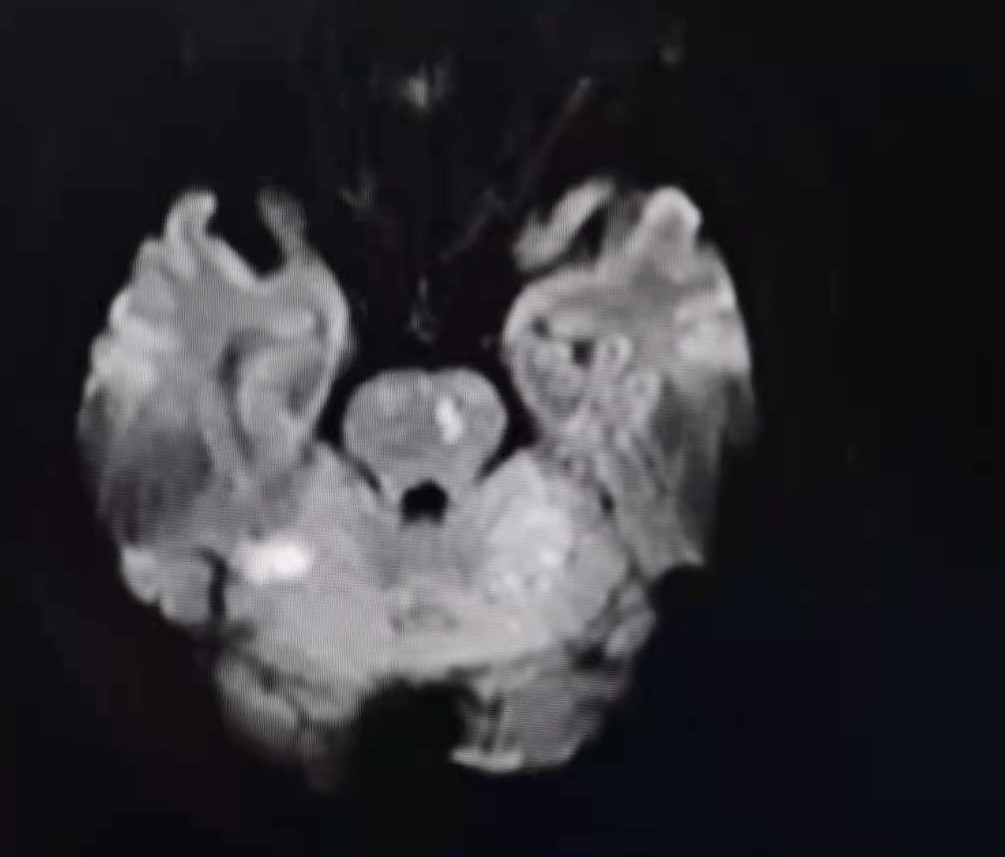

现病史:患者入院2小时余前晨起后被家人发现言语不清、右侧肢体活动不灵,伴头晕、恶心,未吐,症状持续不缓解,急查颅脑CT未见出血。

入院颅脑CT未见出血。

病人的选择:颅内动脉闭塞再通一定要选择有症状的,标准药物治疗欠佳病人。如果是前循环,可以术前完善灌注成像,选择失代偿的病人。最好选择近期闭塞的病人,时间越长斑块越硬,血管床破坏越重,开通成功率越低。有时不好判断闭塞时间,患者近期有缺血事件发生,提示有可能近期发生闭塞。闭塞节段最好不要超过15mm,有时可以通过高分辨磁共振对闭塞节段的长短和血管床情况进行评估。该病人因为有吻合血管,远端血管床显影,可以直接判断闭塞节段不超过15mm。